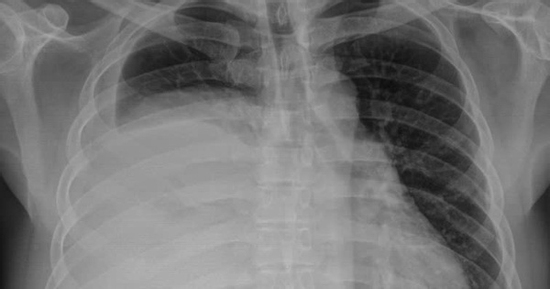

Người đàn ông 42 tuổi mang khối u nặng 3,6kg trong lồng ngực mà không biết

Khối u trung thất khổng lồ, có kích thước lên tới 30x20 cm, nặng 3,6 kg. Đây là một trong những khối u lớn hiếm gặp trong y văn, đe dọa nghiêm trọng đến chức năng hô hấp của người bệnh.